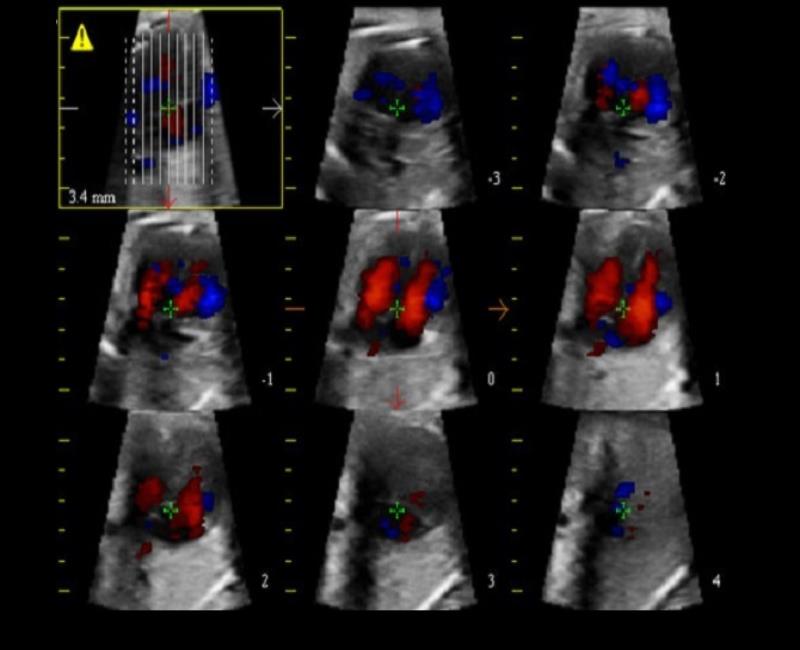

XSTIC - phần mềm phân tích không gian thời gian tim thai.

Siêu âm tim mạch

TVM: bản đồ vận tốc mô với chế độ kép (Doppler màu và Doppler năng lượng).

Xstrain4D - Đánh giá vận động vùng tâm thất trái toàn diện với Siêu âm đánh dấu mô cơ tim 4 chiều.

Siêu âm đánh dấu mô theo 3 hướng: dọc, vòng tròn và xuyên tâm với công nghệ độc quyền và chính xác.